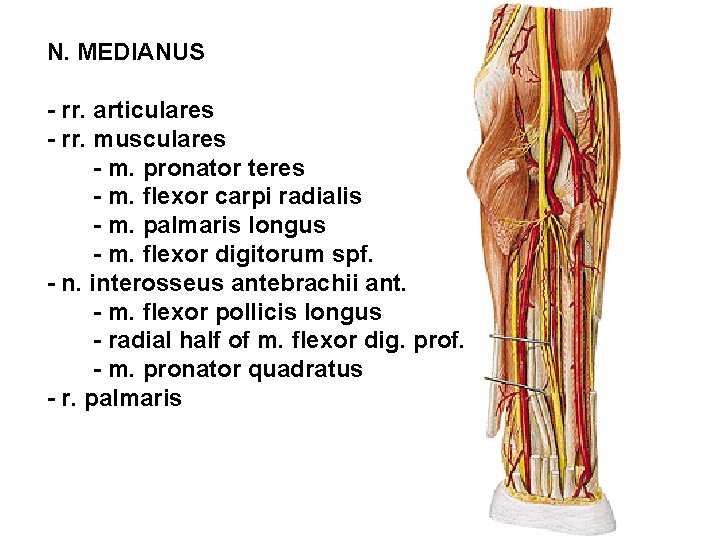

N. MEDIANUS - rr. articulares - rr. musculares - m. pronator teres - m. flexor carpi radialis - m. palmaris longus - m. flexor digitorum spf. - n. interosseus antebrachii ant. - m. flexor pollicis longus - radial half of m. flexor dig. prof. - m. pronator quadratus - r. palmaris

N. MEDIANUS - r. thenaris - m. abductor pollicis brevis - m. flexor pollicis brevis – caput superficiale - m. opponens pollicis - nn. digitales palmares communes - mm. lumbricales (I, II) - nn. digitales palmares proprii - r. communicans cum nervo ulnari